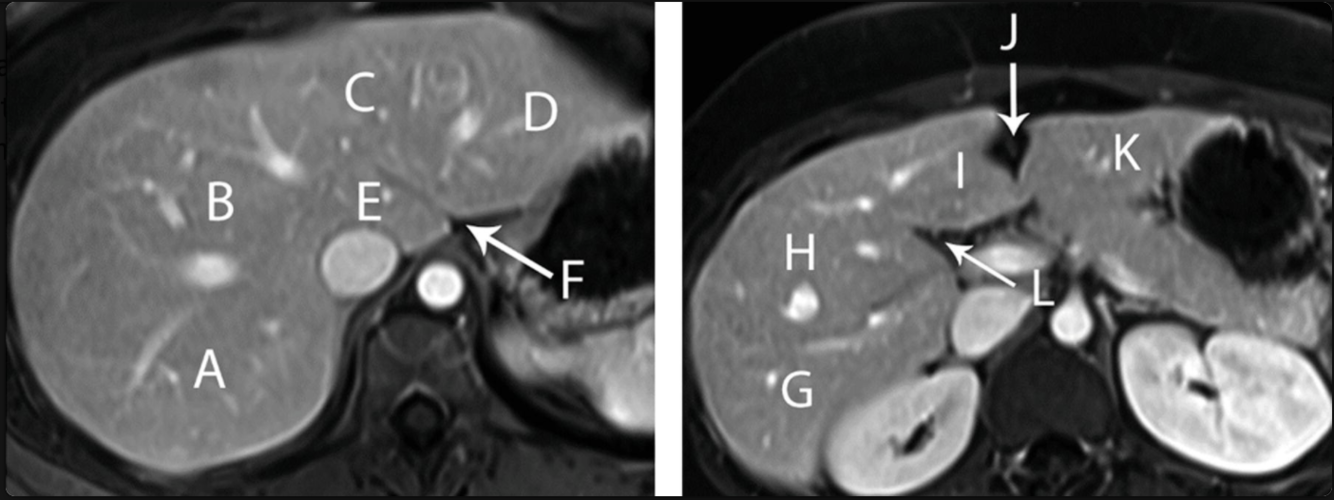

Name each of the structures

A: seg 7

B: seg 8

C: seg 4A

D: seg 2

E: seg 1/caudate

F: fissure of ligamentum venosum

G: seg 6

H: seg 5

I: 4B

J: fissure for falciform ligament

K: seg 3

L: interlobar fissure (for the GB, separates R & L lobes_